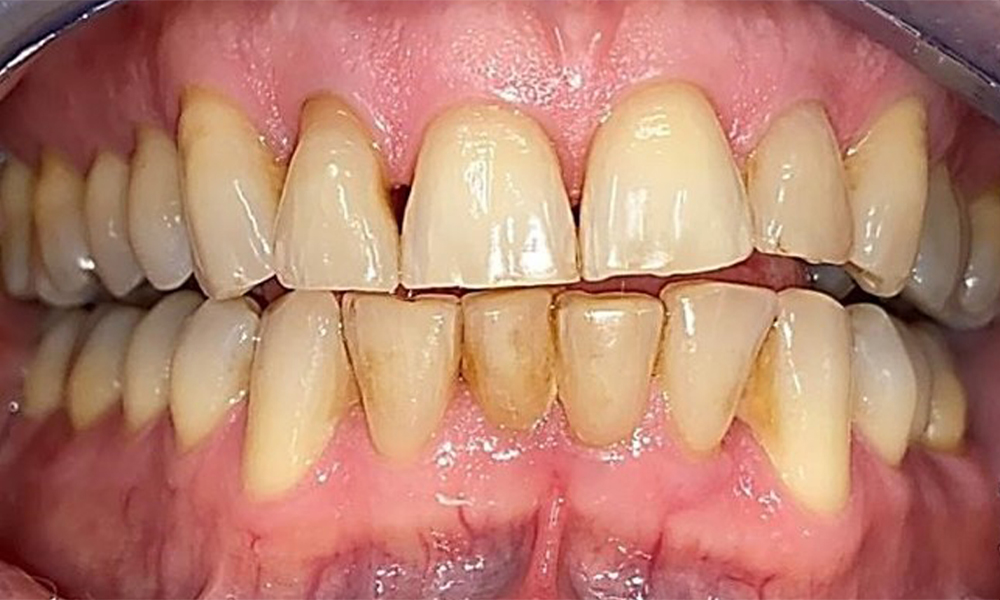

Фронтален изглед със загуба на интерденталната папила между 12 и 11.

Фиг. 2 Фронтален изглед със загуба на интерденталната папила между 12 и 11 © д-р Р. Крапф

Десен страничен изглед. Загуба на интерденталните папили.

Фиг. 3 Десен страничен изглед. Загуба на интерденталните папили. © д-р Р. Крапф

Изглед от лявата страна, включващ рецесиите.

Фиг. 4 Изглед от лявата страна, включващ рецесиите. © д-р Р. Крапф

Пациентът има пълно съзъбие с 28 зъба, което включва амалгамни и композитни пломби в областта на моларите и премоларите. На зъб 14 има видима клинична маргинална празнина. Зъб 27 има адекватна златна инкрустация. Налице са и генерализирани атриции и абразии. (фиг. 2, фиг. 3, фиг. 4, фиг. 5, фиг. 6)

Пациентът е с пародонтит II стадий, степен В (5). Клиничните дълбочини на сондиране от 1 до 3 mm са във физиологичния диапазон. Локализирани дълбочини на сондиране от 5 mm са наблюдавани медиопалатинално на 17 и 27. Налице са генерализирани рецесии от 1 до 3 mm с частична загуба на интердентални папили (фиг. 2, фиг. 3, фиг. 4)